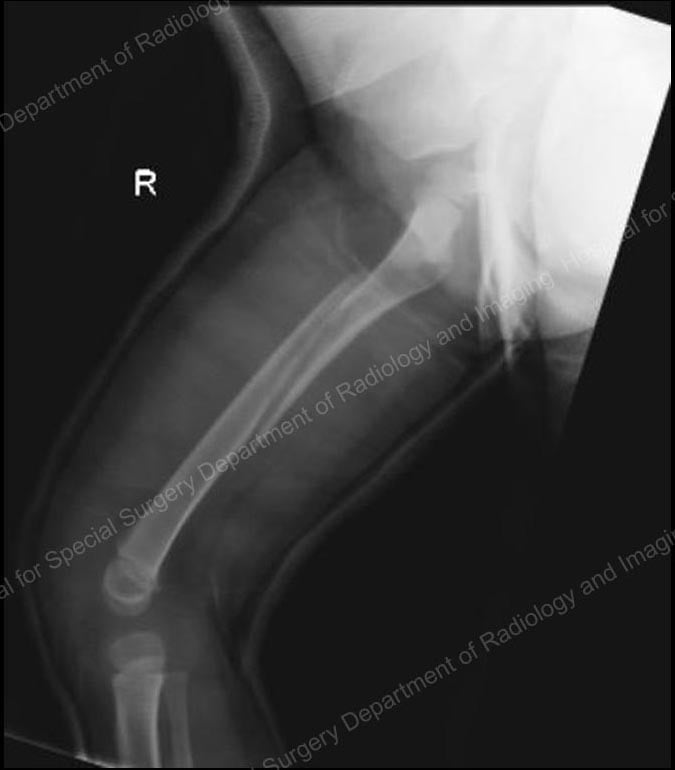

Since the early 2000s, many pediatric orthopedists have started using intramedullary nails or rods made from strong, lightweight, and flexible titanium to stabilize femur fractures in children aged five and older. In a relatively simple technique, the orthopedic surgeon makes two small incisions − about one inch in length − on either side of the knee. After the bone is realigned, the nails are inserted up through the center of the bone where they act as an internal splint during healing.

X-ray showing flexible intramedullary nails in place.

Intramedullary nails come in a range of diameters to accommodate the varying size of children’s bones. Generally no casting is necessary, however a knee immobilizer is commonly used for a few weeks to prevent movement and to keep the child comfortable. In most cases, a recovery period of three to six weeks of early healing is necessary before the child can begin walking on the injured leg. When the bone is completely healed, usually around one year after the injury occurs, the child returns to the hospital to have the nails removed.

Intramedullary nails are usually very well-tolerated. They are particularly useful in five- to ten-year-old children who have a thick lining around the bone called the periosteum, which might be likened to the peel on a banana. The periosteum helps keep the bone more stable and reduces the need for a heavy and rigid device, such as those that might be used in adults.